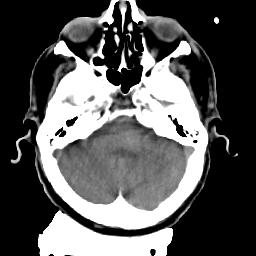

Meningioma: Roentgen-ray CT #2 -- Slice #4

[Home][Help][Clinical] Slice 4